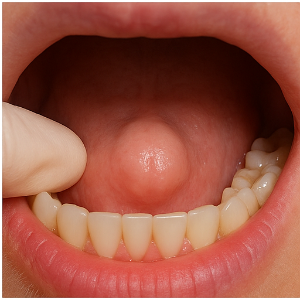

입 안쪽 잇몸에 단단한 혹처럼 느껴지는 돌출이 나타날 때, 이를 흔히 골융기(骨隆起)라고 합니다. 실제로는 혹이 아니라, 잇몸 아래 뼈가 과하게 자라서 돌출된 구조예요. 단단하고 움직이지 않으며, 보통 통증은 없답니다. 원인은 뚜렷하지 않지만, 선천적으로 갖고 태어나는 경우도 있고, 나이가 들며 조금씩 자라기도 해요.

- 딱딱하고 단단한 혹처럼 올라와요.

- 표면이 매끈하거나 둥글게 보이기도 하고, 울퉁불퉁하거나 튀어나온 형태인 경우도 있어요.

다른 가능성도 있는데요, 골융기와 비슷하게 염증 등 다른 원인 때문에도 잇몸이 불룩하게 느껴질 수 있어요. 예를 들어 치주농양 같은 경우는 염증 때문에 부푼 모습이 흔히 '혹처럼' 느껴질 수 있고, 통증이나 고름, 잇몸 붓기 등의 증상이 동반될 수 있죠.